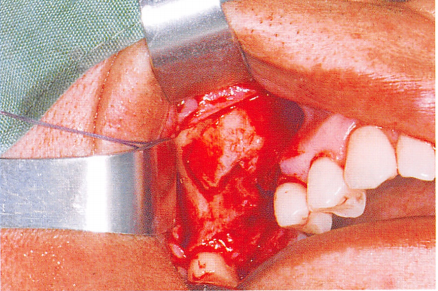

(一)切开

第一步:牙槽嵴顶切口,以执笔式持手术刀,切开前必须找一个可靠的支点,多以余留牙为支点,运刀时必须做到稳和准。

对于牙龈覆盖区域或者牙槽骨面较平整的牙槽黏膜覆盖区域,可以一刀切至骨膜下,对于牙槽骨表面不平整的牙槽黏膜覆盖区域,可以分两次切开,先切开黏膜表层,然后再切至骨膜下,此种方式的优点是容易做到切缘整齐,且准确层次清晰。

第二步:龈沟内切口,从龈沟内插入,直达牙槽嵴顶,紧贴牙面运刀,不可伤及游离龈缘。分离要完全,以免翻瓣时造成牙龈撕裂。

第三步:行纵向切口,从龈沟底向龈缘运刀,避开牙龈乳头,止于轴面角,形成外斜切口。

第四步:减张切口,可松解延长组织瓣,用来严密关闭创面。